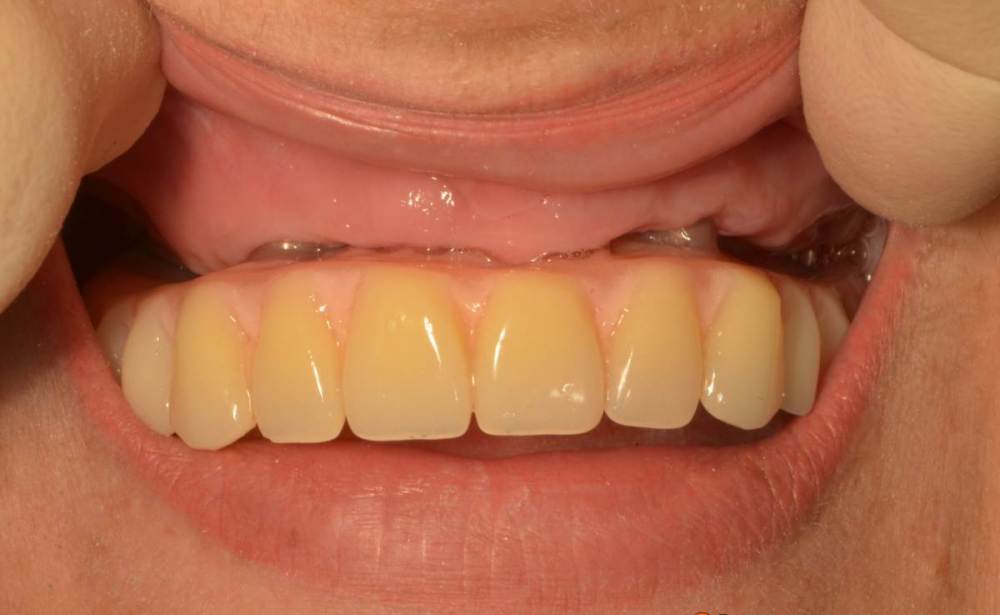

Большой Зеленый Опубликовано 2 октября, 2023 Автор Поделиться Опубликовано 2 октября, 2023 Зубы удалил предварительно. Толкать импланты в гной нехорошо. Ссылка на комментарий

Большой Зеленый Опубликовано 3 октября, 2023 Автор Поделиться Опубликовано 3 октября, 2023 Везде воспаление было. зубы оставшиеся точно не помощники были. Ссылка на комментарий